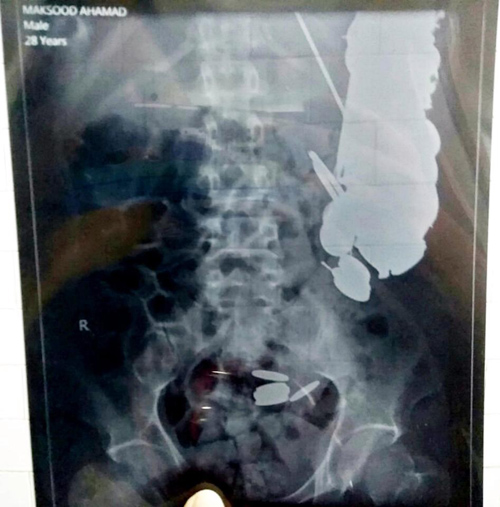

28/11/2017 16:54Người đàn ông có 263 đồng xu và 100 móng tay trong bụng

Anh Maksud Khan (35 tuổi) được đưa vào bệnh viện vì nghi ngờ ngộ độc thực phẩm sau khi đau bụng dữ dội. Theo The Sun, các bác sĩ đã thực hiện nội soi để điều tra nguyên nhân. Họ kinh ngạc khi thấy hàng trăm đồng xu, 1,5 kg móng tay, hàng chục rao cạo râu, mảnh thủy tinh, đá và đinh sắt bị gỉ trong bụng người này.

Các bác sĩ ngay lập tức phẫu thuật và lấy đi tất cả những vật thể trên, tổng cộng tới 7 kg. Khan được cho là có vấn đề về sức khỏe tâm thần và không cho gia đình hoặc bạn bè biết về thói quen ăn uống kỳ quặc của mình.

Bác sĩ Priyank Sharma, trưởng ca phẫu thuật, nói: "Bệnh nhân than phiền đau dạ dày, vì vậy chúng tôi đã làm nội soi. Chúng tôi bị sốc khi phát hiện ra tiền xu, móng tay và đinh ốc trong bụng. Người đàn ông này trông có vẻ không ổn định về thần kinh vì không có người bình thường nào làm điều đó".

Theo các bác sĩ, anh Khan làm công việc lái xe tuk-tuk và thường nuốt những đồng tiền do khách hàng trả cho. Khan đã kêu ca về cơn đau dạ dày trong 3 tháng qua.

Một bác sĩ điều trị cho Khan tiết lộ: "Một số chiếc đinh đã đâm vào dạ dày của anh này, gây chảy máu và dẫn đến giảm hồng cầu".